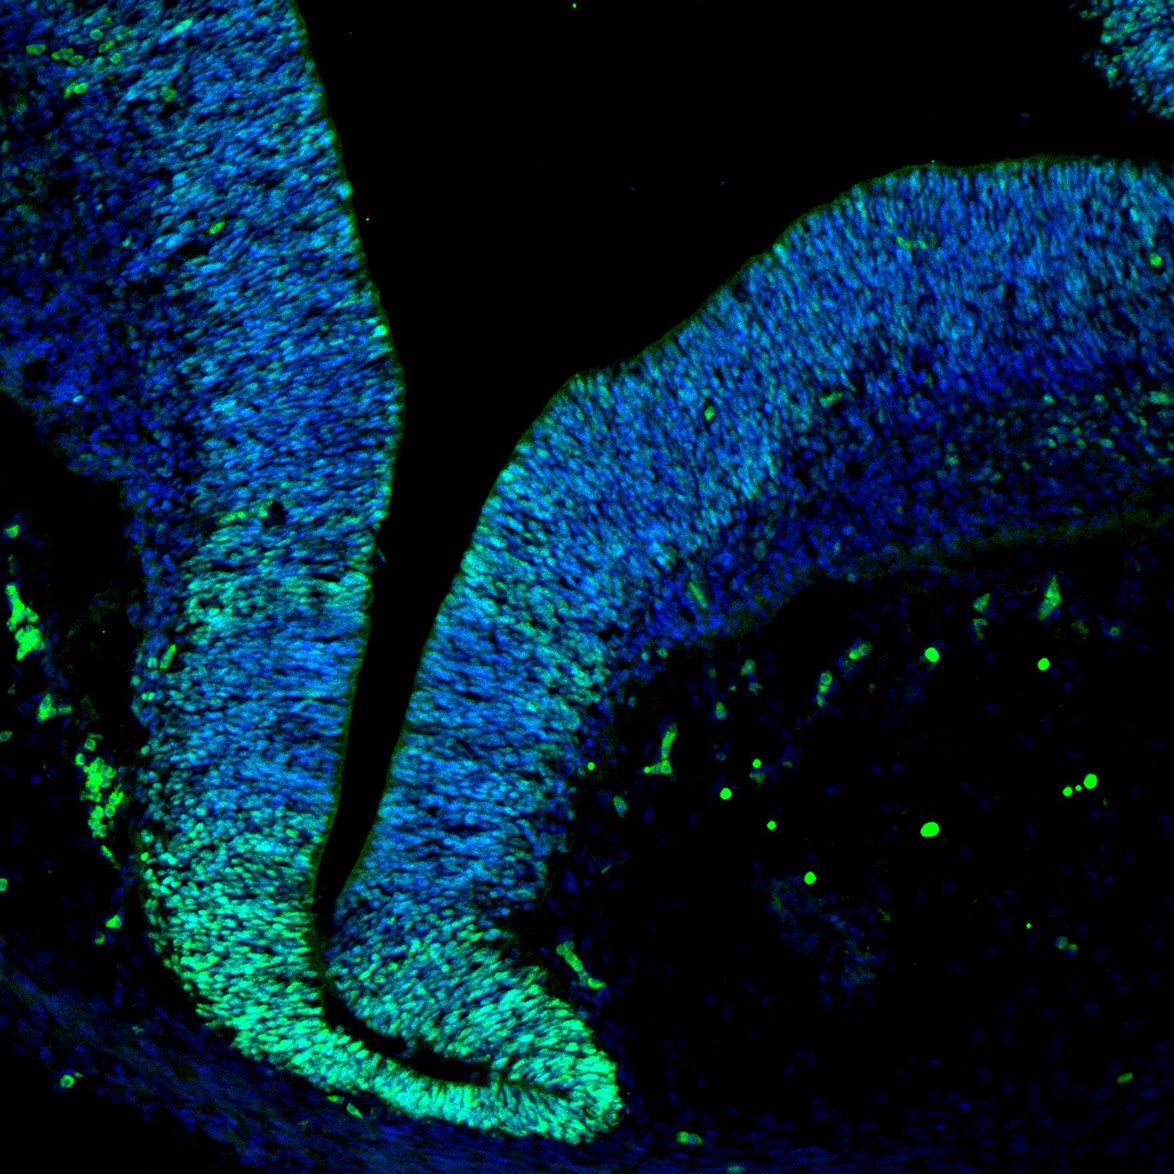

An anatomical analysis of the developing human midbrain from 6 post-conceptional weeks (PCW) to 22 PCW reveals increased tissue complexity, characterized by the emergence of dopaminergic nuclei, as highlighted by immunofluorescence analysis for tyrosine hydroxylase (TH).

SOX2

11PCW human midbrain

Merged